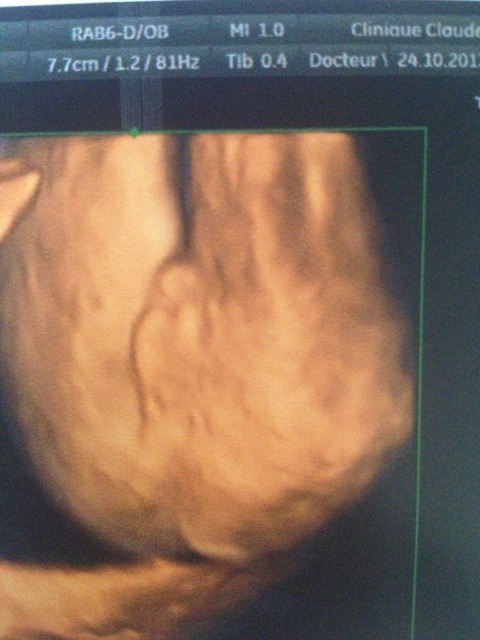

Echo 5 2eme Trimestre 22 Sa 4 Sexe Et Morphologie Enviedefraises

Echo 22 Sa Toi Moi Et Oceane Denis Aurea Et Petite Anthea Accouchement Prevu Le Fevrier 14

Echo 22sa 3d Futur Bebe 3 Es T Elle Photos Club Doctissimo

Echographie Semaines Fille Part 2 2d 3d 4d Youtube